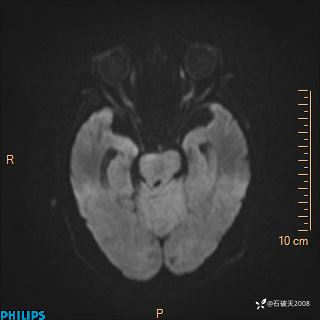

DWI

ADC